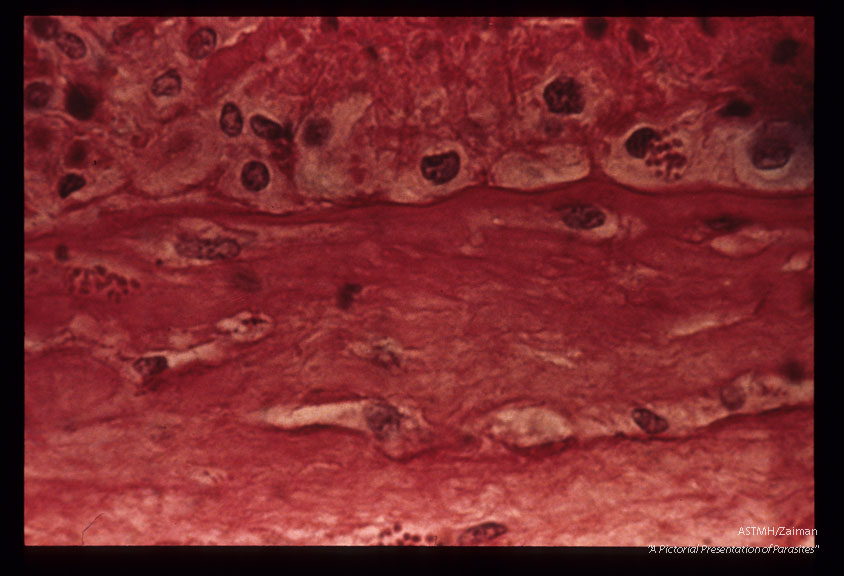

Two groups in chorion, one in the decidua of a human placenta . H&E stain.

Toxoplasma gondii

Description: Two groups in chorion, one in the decidua of a human placenta . H&E stain.